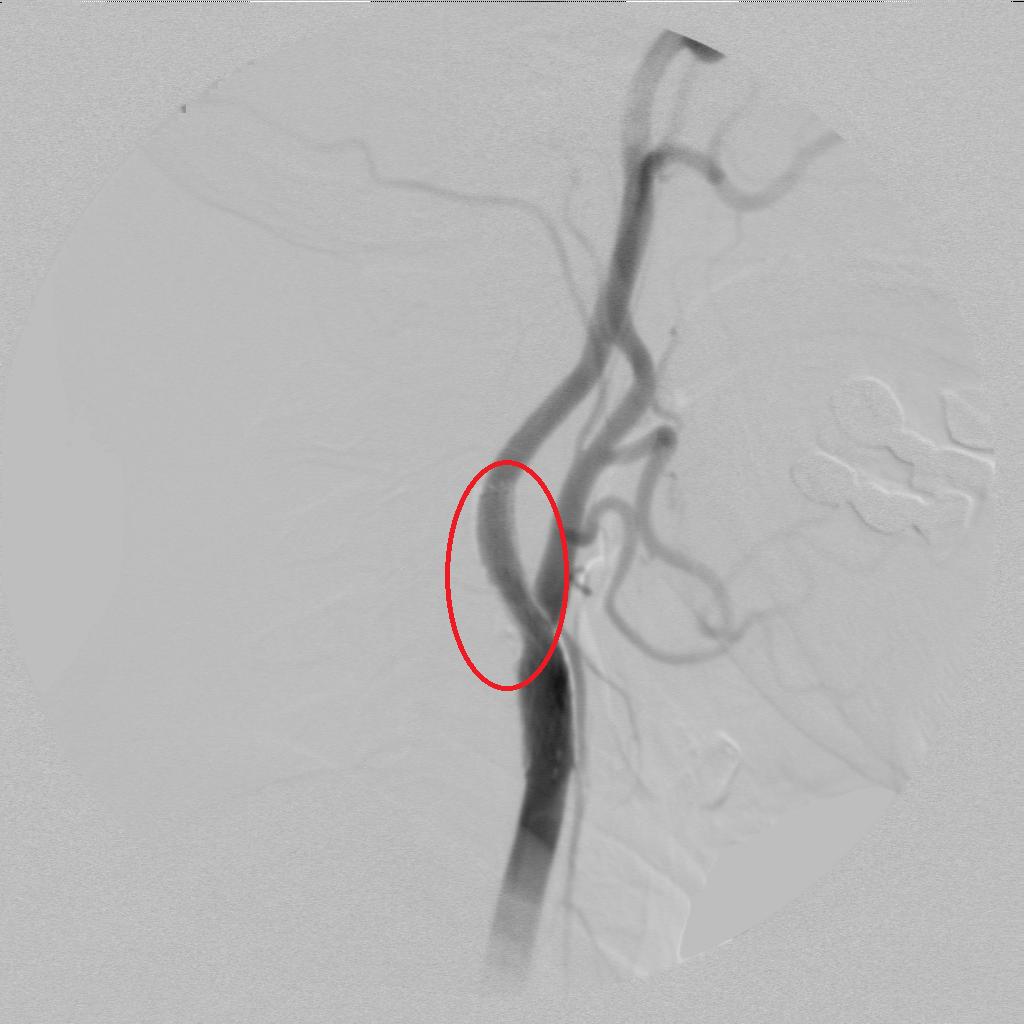

术后动脉狭窄明显恢复!